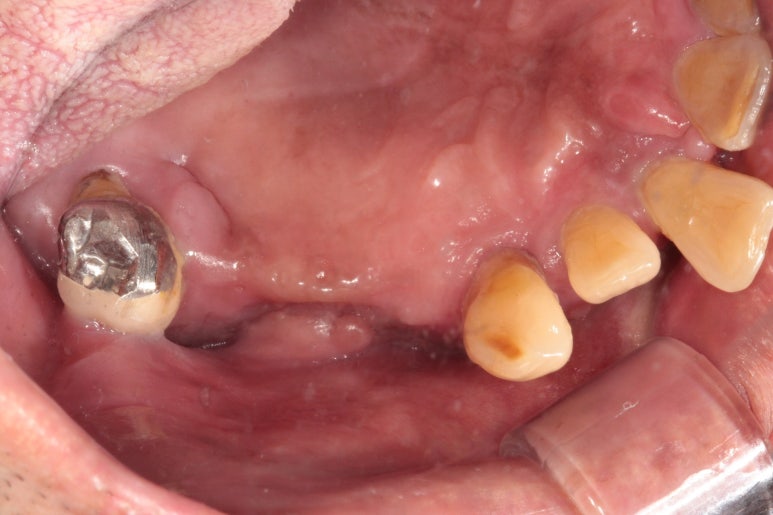

그나마 큰 어금니가 한 개 남은 오른쪽 위 구강 내 사진입니다.

딱 보시면 아시다시피, 만성치주염(풍치)를 심하게 앓고나서 치아를 빼면.. 남는 잇몸뼈가 별로 없습니다. 다 위축되서.. 임플란트 심기 곤란한 상황이 많이 생기죠.

그래서 더더욱이 치주염 치료를 위해 정기검진을 챙기셔야 하는 이유랍니다.

아래 앞니도 상당히 좁아져버린 잇몸뼈의 모양을 관찰하실 수 있을거에요.

이런 부위는 임플란트를 심어내기에도 어려워져 버린답니다.